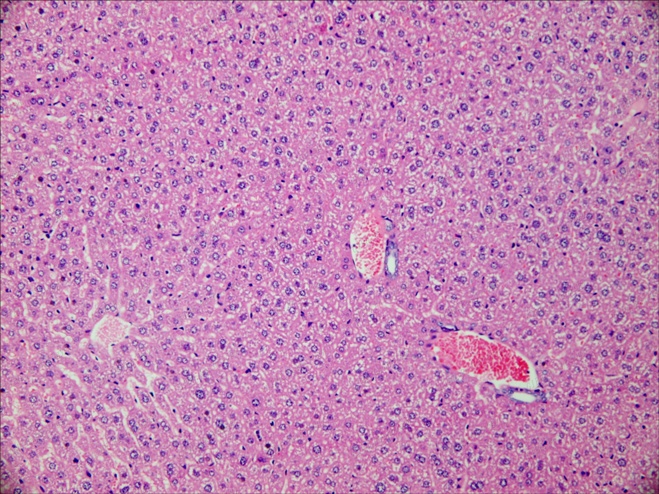

肝 20